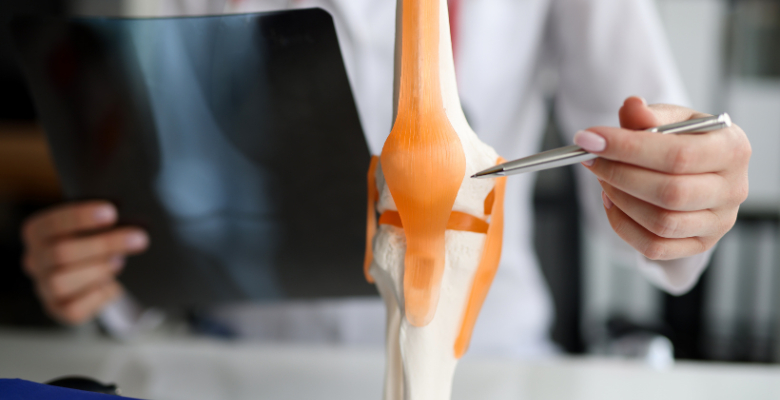

A Sociedade Portuguesa de Endocrinologia, Diabetes e Metabolismo (SPEDM) integra, habitualmente, no programa científico do Congresso Português de Endrocrinologia, temáticas relacionadas com a doença reumatológica, como é o caso da problemática do metabolismo do osso. Nesta 75.ª edição, haverá um simpósio inteiramente dedicado a esta patologia.